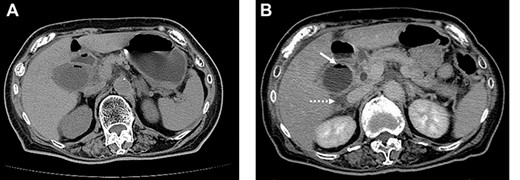

A 79-year-old female with a history of a cerebral infarction was admitted to our hospital due to nausea, epigastric pain and watery diarrhea. Laboratory findings at presentation were notable for elevated white blood cell (WBC) count of 10 400/μl (normal level, <8600/μl) and C-reactive protein (CRP) 0.5 mg/dl (normal level, <0.1 mg/dl). Abdominal computed tomography (CT) revealed that acute cholecystitis with thickening of the gallbladder wall and the gas image within the gallbladder, leading to a diagnosis of EC (Fig. 1A). Despite the diagnosis of EC, her abnormal clinical and laboratory findings were slight. So the decision was made to admit her to the internal medicine department for conservative management with antimicrobial therapy. However, the following day she developed severe abdominal pain with muscular defense. At that time, WBC was 12 500/μl and CRP had further increased to 12.5 mg/dl. Repeat CT revealed increased gas within the gallbladder and newly developed pericholecystic fluid (Fig. 1B), prompting transfer to the surgery department and emergent laparoscopic intervention.

On admission, abdominal computed tomography (CT) scan showed a gas-fluid level in the gallbladder and surrounding fatty infiltration with ascites (A). On hospital day 2, abdominal CT revealed increased gas within the gallbladder (B, white arrow) and the development of pericholecystic fluid (B, dot arrow).